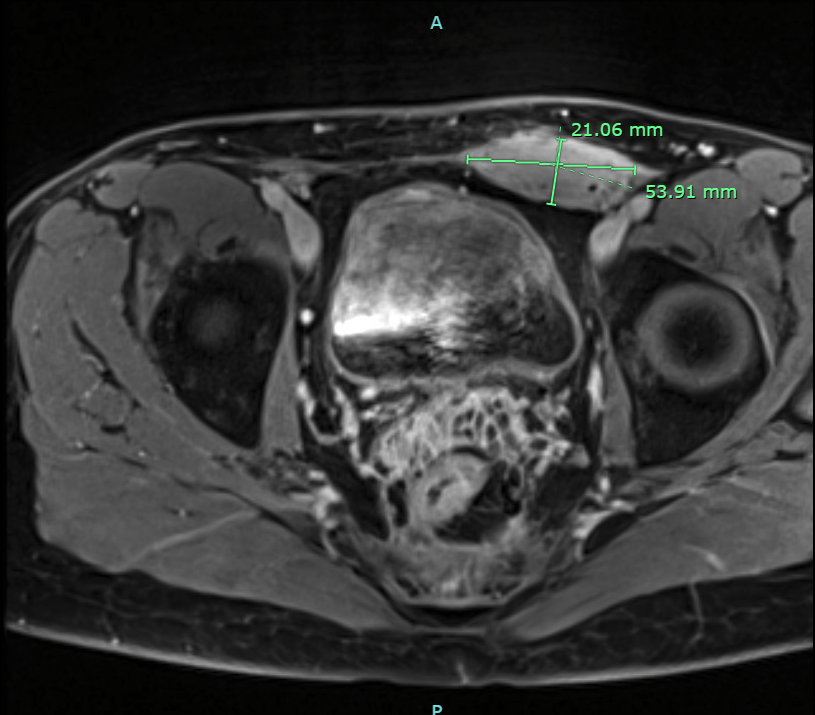

T1 weighted MRI, transverse image of soft tissue thickening with homogenous enhancement of the lower rectus abdominis muscle.